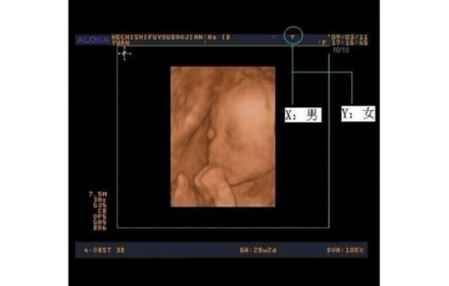

三、看b超单

孕妇在中晚期做B超时,可留心任意一张B超单(早孕的不能显示的),看看B超图像上最顶是不是有一橫行,橫行中间会有显示Y或X的字母,如果是Y就代表你怀的是女孩,X就是男孩。不过有的地方很严格,B超单上可能没有。